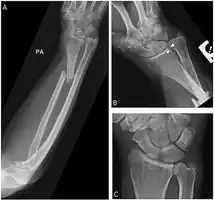

Galeazzi fracture

| Galeazzi fracture-dislocation | |

| Galeazzi fracture. Arrow points at the dislocated ulnar head | |

The Galeazzi fracture is a fracture of the distal third of the radius with dislocation of the distal radioulnar joint. It classically involves an isolated fracture of the junction of the distal third and middle third of the radius with associated subluxation or dislocation of the distal radio-ulnar joint; the injury disrupts the forearm axis joint.[1]

The dislocation of ulnar head in Galeazzi fracture dislocation may be dorsal (commoner) or volar (rare) depending on the mechanism of injury. If the fall is on the outstretched hand with forearm in pronation, the dislocation is dorsal, and if forearm is in supination at the time of injury, the dislocation is volar.[2]

Galeazzi fractures are best treated with open reduction of the radius and the distal radio-ulnar joint.[3] It has been called the "fracture of necessity," because it necessitates open surgical treatment in the adult.[4] Nonsurgical treatment results in persistent or recurrent dislocations of the distal ulna.[1] However, in skeletally immature patients such as children, the fracture is typically treated with closed reduction.[1]